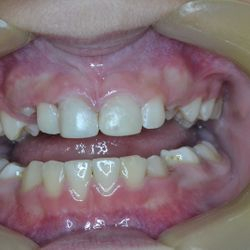

This young patient had completed an orthodontic treatment which had led to pulp necrosis in her upper right central and lateral incisor.

The teeth were root-treated and as a result, they were discolored.

We re-enforced the strength of these teeth using aesthetic fiber posts and restored their shade with nanotechnology composite resin veneers.